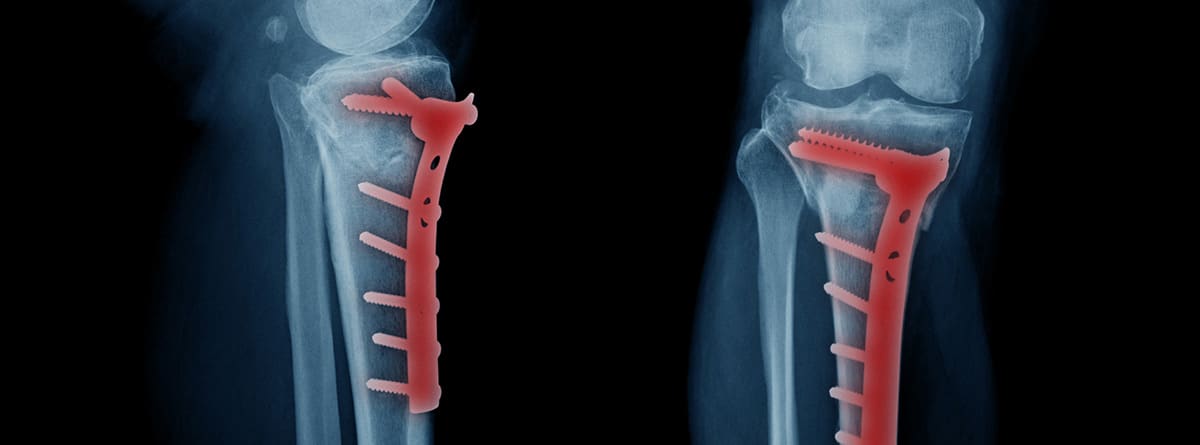

- Placas: fabricadas en titanio o acero inoxidable, se colocan sobre la superficie ósea y se aseguran con tornillos. Se utilizan sobre todo en fracturas de huesos largos.

- Clavos intramedulares: introducidos en la década de 1940, este tipo de material está diseñado para la colocación intramedular en huesos largos, tales como el fémur, la tibia o el húmero.

En estas imágenes vemos una fractura de fémur tratada con placa atornillada y otra con un clavo que va por dentro del hueso. Utilizar uno u otro sistema depende de la fractura.